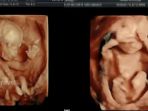

Merinding! Bayi ini Melambai dan Melakukan Gerakan Ciluk Ba Ketika di-USG 4D

Sebuah rekaman menakjubkan memperperlihatkan bagaimana seorang bayi yang masih di dalam rahim berusia 16 minggu melambai kepada kedua orang tuanya.

Sabtu, 28 Januari 2017 -